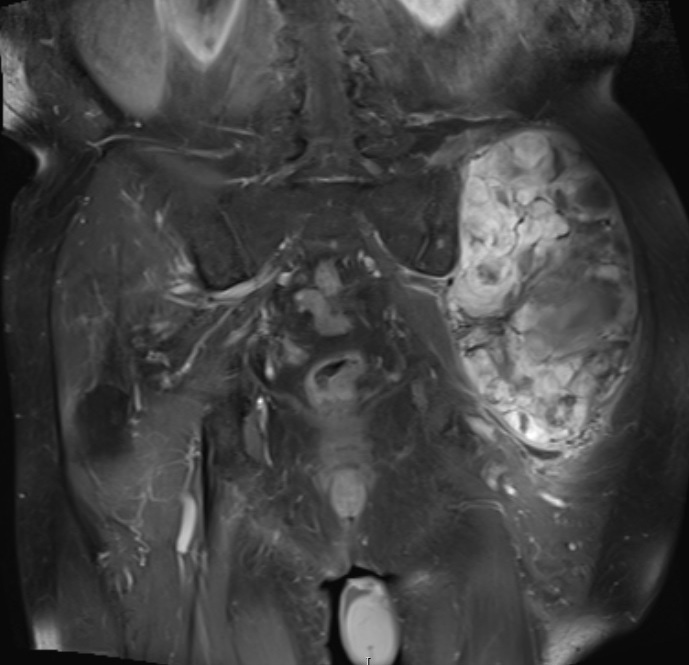

Fig. 11 – 13 Axial (Fig. 11), Coronal (Fig. 12) and Sagital (Fig. 13) contrasted T1-weighted MR images show a large heterogeneous mass with central and peripheral

enhancement. Multiple thick trabeculations. Central low signal intensity image is compatible with necrosis and hemorrhage.